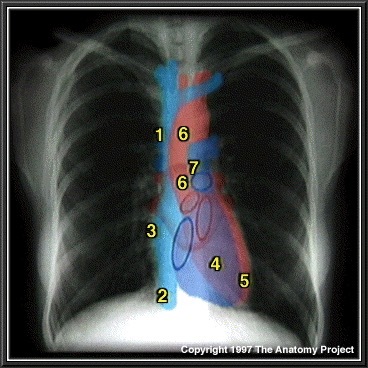

9

What structure is indicated by 1 on the figure below?

A

Superior Vena Cava

10

What structure is indicated by 2 on the figure below?

Inferior Vena Cava

11

What structure is indicated by 3 on the figure below?

Right atrium

12

What structure is indicated by 4 on the figure below?

Right ventricle

13

What structure is indicated by 5 on the figure below?

Left ventricle

14

What structure is indicated by 6 on the figure below?

Ascending Aorta and Aortic Arch

15

What structure is indicated by 7 on the figure below?

Pulmonary vasculature